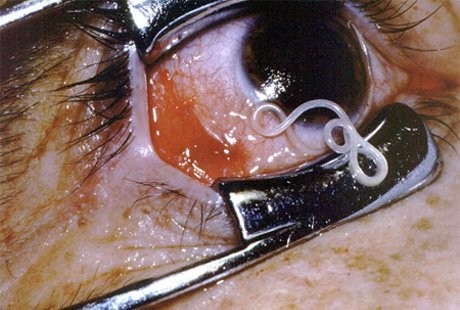

3. Loa Loa, Cacing Mata Afrika

(Foto: oddee)

Cacing ini akan muncul di permukaan bawah bola mata. Kebanyakan cacing ini dapat ditemui di daerah Afrika dan India. Gejalanya sendiri dapat berupa gatal-gatal, nyeri sendi, bahkan kematian.